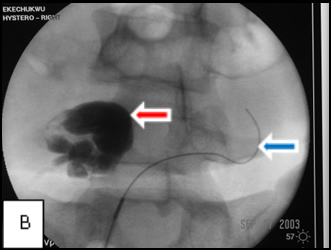

Images A, B, and C belong to a young woman who was referred to me for hysterosalpingography because of infertility and was shown at the examination to have bilateral cornual occlusion of the fallopian tubes. Image A shows contrast opacifying her endometrial cavity (red arrow), but not the fallopian tubes due to bilateral cornual occlusions. In image B, I have reopened the right cornual occlusion, filling a large right hydrosalpinx with radiocontrast (red arrow), and have a guide wire in the left fallopian tube (blue arrow), which implies relief of the obstruction. Image C, the final image, shows that both cornual occlusions are relieved, but there are bilateral large hydrosalpinges because of fimbrial adhesions, proven by the absence of contrast spill into the peritoneal cavity.